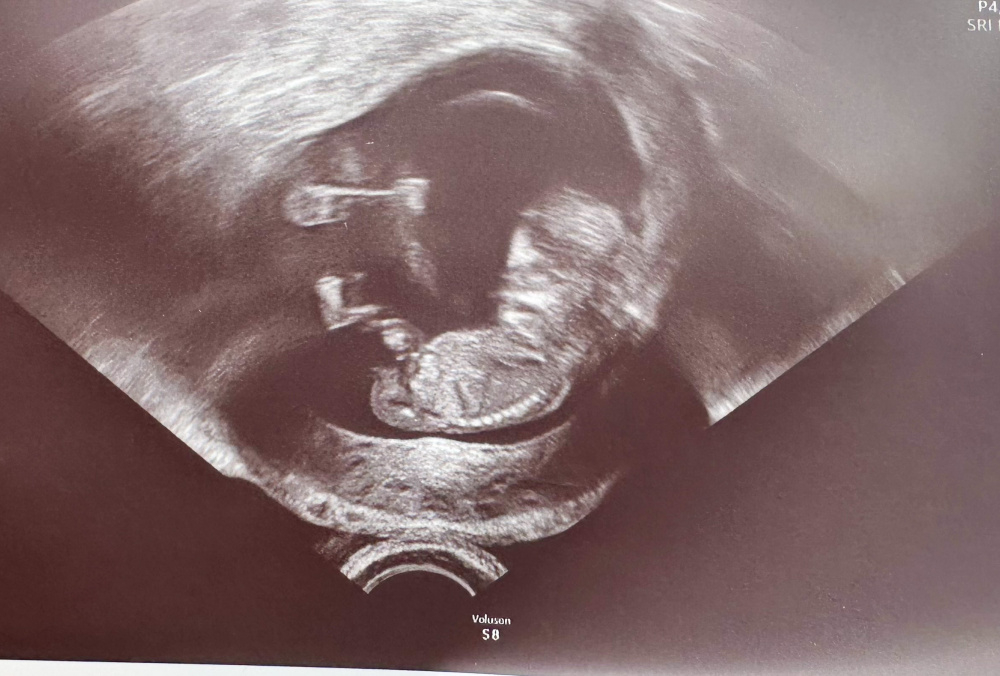

Hallo meine Lieben, waren heute beim Ultraschall SSW17

Das Geschlecht spielt bei uns keine Rolle, da wir bereits einen Jungen und ein MĂ€dchen haben.

Aber aus reiner Neugier, was meint ihr anhand der Bilder, MĂ€dchen oder Junge